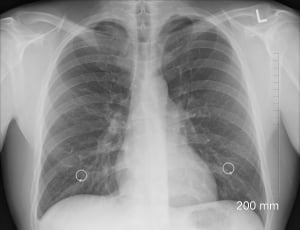

6 royalty free x ray images - PeakpxDebido al rápido crecimiento del uso de la TC pediátrica y al potencial de una mayor exposición a la radiación de los niños que se someten a estas exploraciones, se deben aplicar consideraciones especiales al usar la TC pediátrica. Entre los niños que se han sometido a tomografías computarizadas, aproximadamente un tercio ha tenido al menos tres tomografías. El Instituto Nacional del Cáncer y la Sociedad de Radiología Pediátrica desarrollaron un folleto, Riesgos de radiación y tomografía computarizada pediátrica: una guía para proveedores de atención médica, y la FDA emitió una Notificación de salud pública, Reducción del riesgo de radiación de la tomografía computarizada para pacientes pediátricos y adultos pequeños, que discuten el valor de la TC y la importancia de minimizar la dosis de radiación, especialmente en niños.